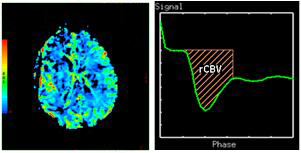

Relative Blood Volume

Relative Blood Volume (rCBV) describes the blood volume of the cerebral capillaries and venules (not arteries) per cerebral tissue volume.